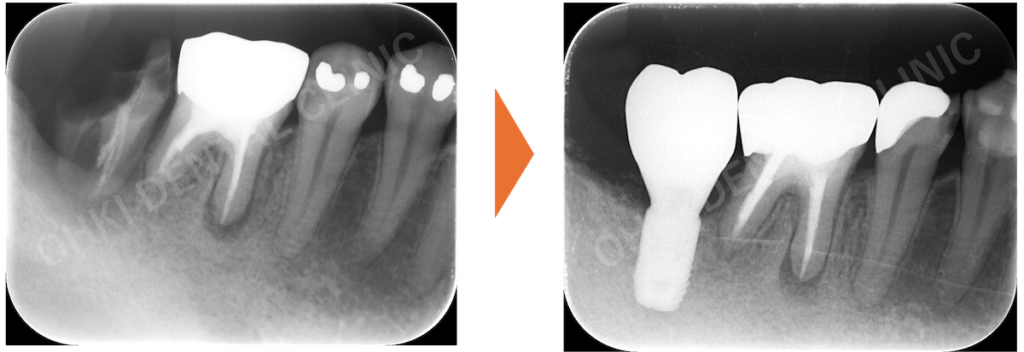

・主訴である右下7番は、コアごと脱離しており、歯根破折を認めました。

・パノラマレントゲン写真では、左下6番にも歯折と周辺の骨吸収が認められました。

抜歯後、骨・軟組織の治癒を待つため、約3ヶ月間の待機期間がありました。 - インプラント埋入:

GBR(骨再生誘導法)を含めたインプラント埋入処置を実施しました。 - 上部構造の装着(ファイナルセット):

歯根破折により周辺に骨吸収が起こっていたため、骨の不足を補うためのGBRも含めて、インプラント治療を実施しました。

- インプラントを埋入したことにより、噛む機能が回復したことが大きな結果です。

- 噛み合わせの柱が再建されたことで、今後、残存している歯の破折リスクや負担が軽減されました。